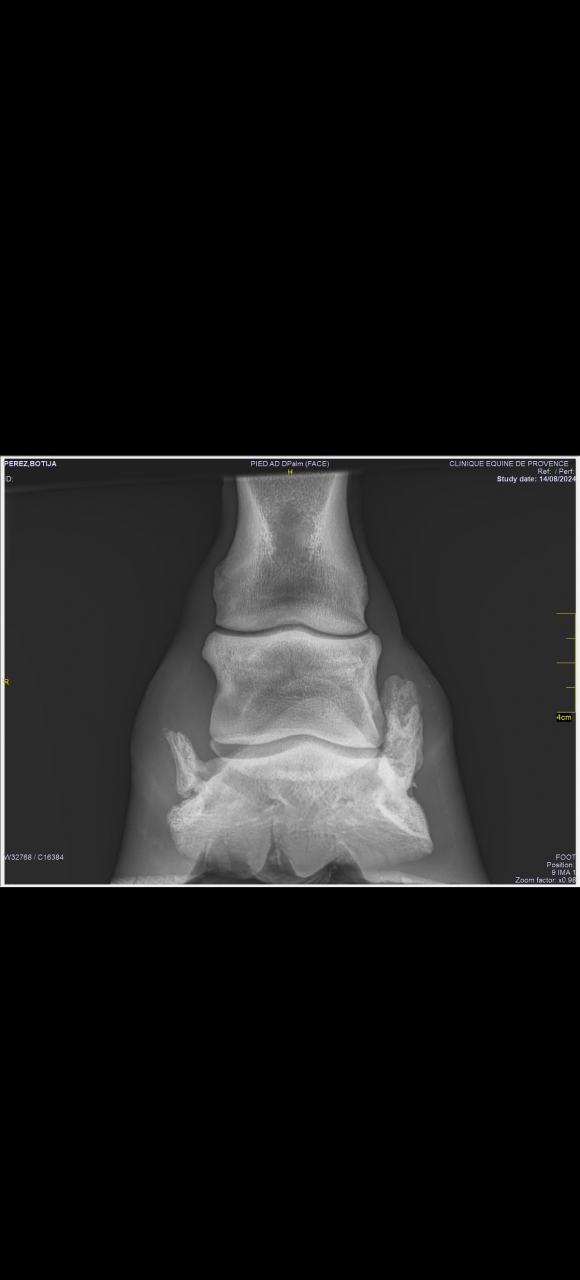

| Dire merci | bon alors... Evidemment le fer génait ce qu'on voit à la radio c'est que le haut jusqu'à la moitié de la "corne" s'opacifie et a moins cet aspect mité donc c'est positif. En revanche on voyait pas le trait de fracture avec le fer mais à la palpation elle a mal (juste au dessus de la couronne).La ferrure est ok, on l'enlève dans 6 semaines, on refait RX et on voit ce qu'on fait. Donc, ça avance, ça nous emmerdera toute notre vie (ça c'est ma compréhension et mon feeling). La véto m'a dit qu'il fallait qu'elle évite absolument de trotter... je vais devoir fermer le paddock plus petit ![]() Bref, ça c'était avant : Lien ![]() [url=https://ibb.co/J5Tm7xz][img]https://i.ibb.co/SRg5nQK/PEREZ-BOTIJA-DX-De-14-08-2024-S4-I0.png" alt="" /> https://ibb.co/7tLbYCq Message édité le 20/09/24 à 13:55 Message édité le 20/09/24 à 13:57 |

| Dire merci | En vrai je suis assez fataliste. Si ça gaze ça gaze et si ça va pas a la monte bah ... Je la monterai pas ... Je vais pas la vendre de toute façon, c'est pas le genre de la maison ![]() Mais bon on en est pas là. ![]() Pour comparer gauche droite ![]() Là ce qui s'est opacifié c'est plutôt la pointe de la calcification, faut donc être patient pour le reste. |